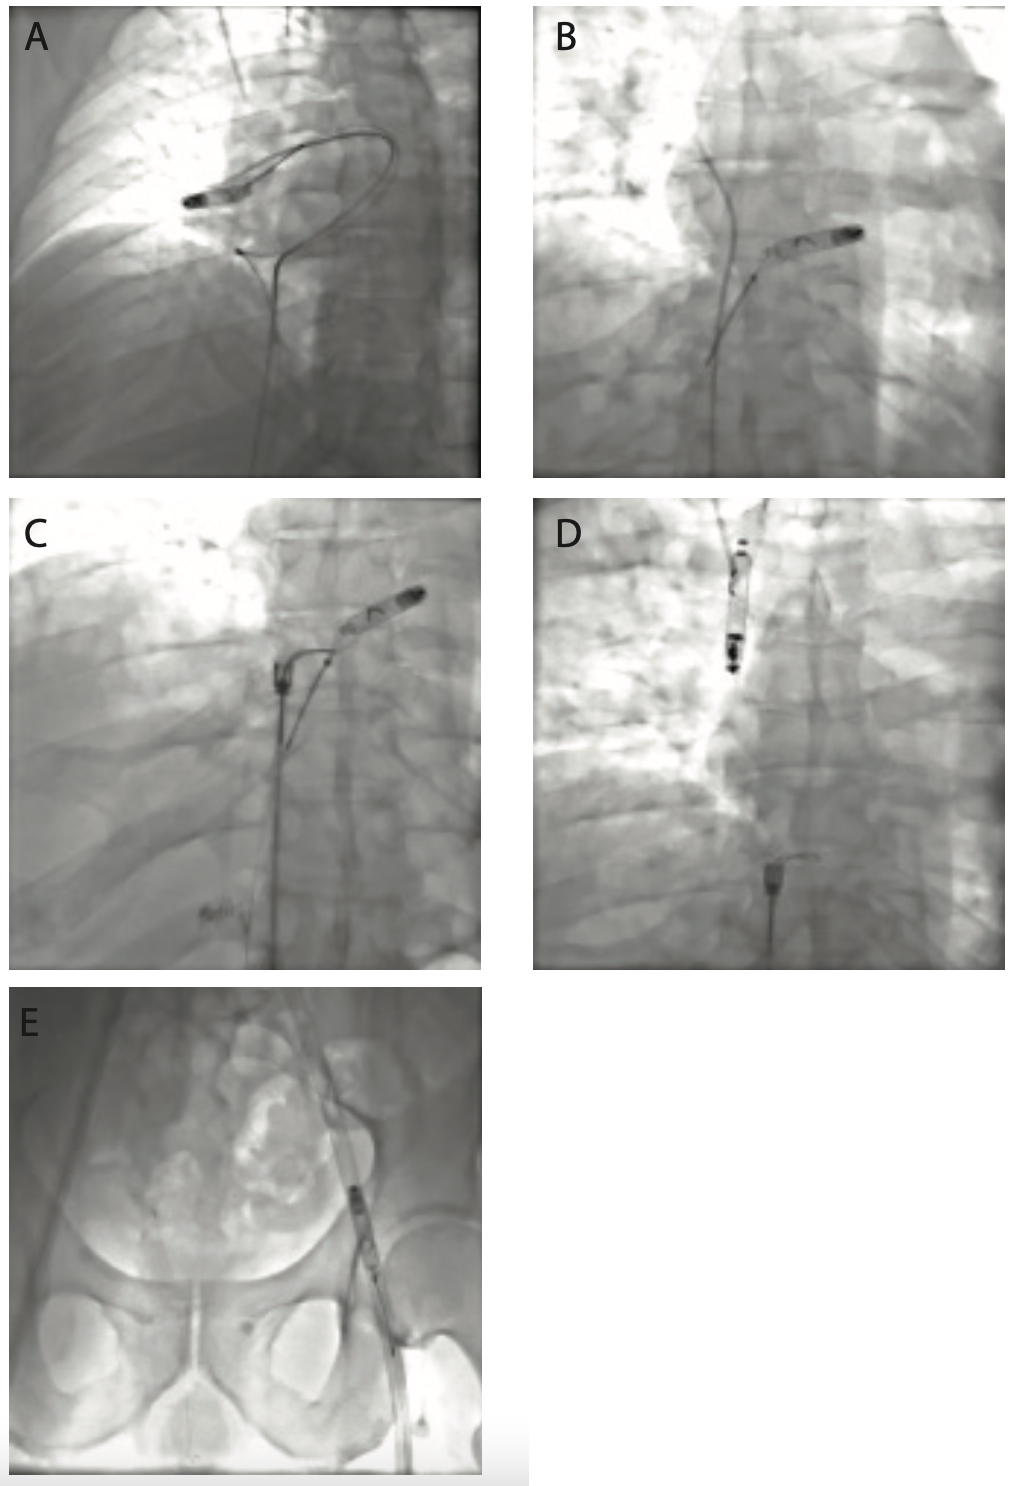

From www.researchgate.net

Results of permanent pacemaker implantation with dual pacing. A The Electrodessication Pacemaker It is safe with electronic equipment, such as pacemakers. Investigate risk of arrhythmia with the patient’s specific pacemaker. The electrosurgical unit is a very useful tool widely used in dermatology to treat benign and malignant skin lesions and to achieve hemostasis during. According to in vitro studies, electrodessication is considered safe in patients with implanted cardiac devices. To the authors'. Electrodessication Pacemaker.